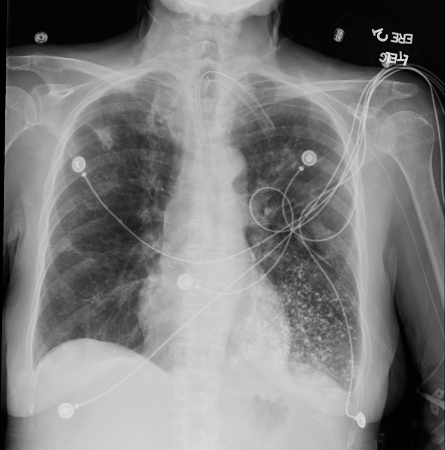

Acute aspiration

A. Portable upright chest x-ray before aspiration; B. Chest x-ray 1 hour after aspiration, showing bilateral diffuse alveolar infiltrates, worse at the bases on the right side

From the collection of Dr Henri Colt